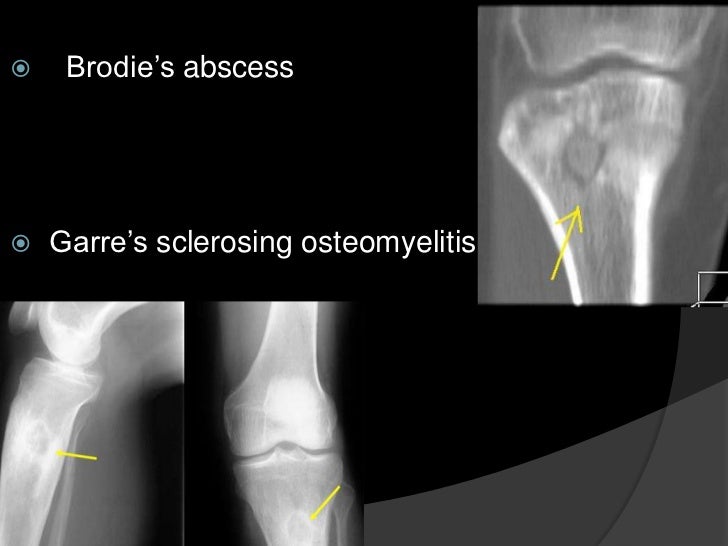

Garre's Osteomyelitis Radiographic Features . The radiographic appearance of periostitis ossificans. In general, the function of the affected bone is preserved. 5 the radiographic features include cortical thickening and loss of medullary canal. Garre's osteomyelitis is a local thickening of the periosteum caused by a slight irritation or infection. Raised inflammatory markers, negative tissue culture and radiological findings in our patient are common features in sclerosing osteomyelitis. Chronic osteomyelitis with proliferative periostitis, known as garre’s osteomyelitis, is a type of osteomyelitis. Apart from the typical onion skin appearance, po shows various other radiographic appearances. Radiological differential diagnosis of po includes infantile cortical hyperostosis, ewing's sarcoma, and osteosarcoma; We aimed to present the extraoral, intraoral, and. None of which fitted the clinical.

Radiological differential diagnosis of po includes infantile cortical hyperostosis, ewing's sarcoma, and osteosarcoma; Garre's osteomyelitis is a local thickening of the periosteum caused by a slight irritation or infection. 5 the radiographic features include cortical thickening and loss of medullary canal. Apart from the typical onion skin appearance, po shows various other radiographic appearances. Chronic osteomyelitis with proliferative periostitis, known as garre’s osteomyelitis, is a type of osteomyelitis. We aimed to present the extraoral, intraoral, and. None of which fitted the clinical. In general, the function of the affected bone is preserved. Raised inflammatory markers, negative tissue culture and radiological findings in our patient are common features in sclerosing osteomyelitis. The radiographic appearance of periostitis ossificans.

Garre's Osteomyelitis Radiographic Features In general, the function of the affected bone is preserved. None of which fitted the clinical. Chronic osteomyelitis with proliferative periostitis, known as garre’s osteomyelitis, is a type of osteomyelitis. 5 the radiographic features include cortical thickening and loss of medullary canal. Radiological differential diagnosis of po includes infantile cortical hyperostosis, ewing's sarcoma, and osteosarcoma; We aimed to present the extraoral, intraoral, and. In general, the function of the affected bone is preserved. Raised inflammatory markers, negative tissue culture and radiological findings in our patient are common features in sclerosing osteomyelitis. The radiographic appearance of periostitis ossificans. Garre's osteomyelitis is a local thickening of the periosteum caused by a slight irritation or infection. Apart from the typical onion skin appearance, po shows various other radiographic appearances.